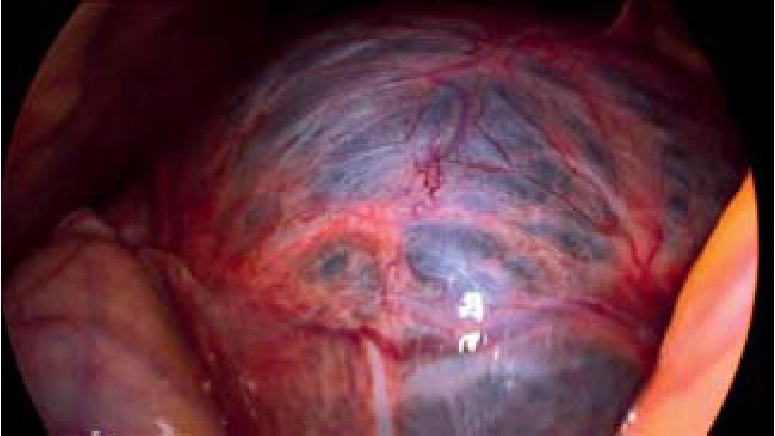

В параумбиликальной области установлен лапаропорт с оптической системой. При ревизии – в брюшной полости выпота нет. В проекции IV, V и VIII сегментов печени визуализирована киста размерами 18×18×12 см (рис. 2).

Рис. 2. Интраоперационная картина кисты печени

Выполнена пункция кисты печени – получено около 2000 мл прозрачного экссудата. Стенки кисты иссечены с помощью аппарата «LigaSure». Ложе кисты тщательно обработано аргоноплазменной коагуляцией (рис. 3). Аргон под действием электрического поля достаточно легко ионизируется и превращается в плазму, которая направляется в ткани с наименьшим электрическим сопротивлением, вызывая таким образом коагуляцию. Данная методика обработки ложа кисты имеет ряд преимуществ перед обработкой электрокоагуляцией: отсутствие прилипания и минимальная травматизация окружающих тканей, стойкая, но при этом неглубокая (до 3 мм) коагуляция, а также минимальное дымообразование, что очень важно в лапароскопической хирургии. Кроме того, отмечается антимикробное воздействие аргоновой плазмы на обрабатываемую поверхность при бесконтактном использовании [1, 17].

Рис. 3. Вид операционного поля во время и после обработки аргоноплазменным потоком